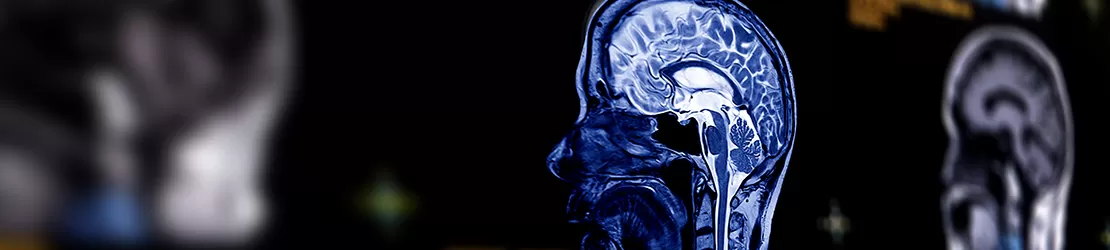

Imagine RMN a creierului in plan sagital, cu detalii selective, ilustrand structura interna a creierului pentru diagnosticul cavernomului cerebral.

• rezonanță magnetică (RM), inclusiv cu secvențe speciale pentru analiza hemoragiilor (GRE, SWI): este prima investigație recomandată de medicii MedLife, foarte sensibilă pentru cavernom;